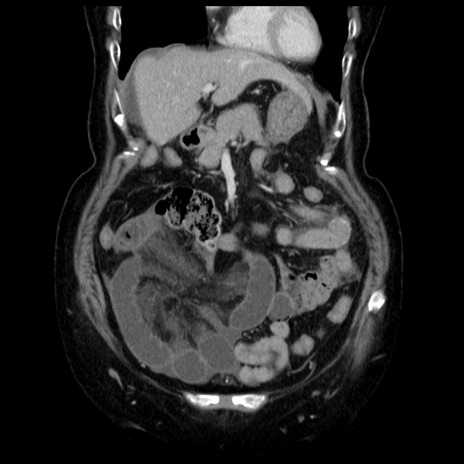

症例13(冠状断像)

【症例】70歳代女性

【主訴】腹痛、嘔吐

【現病歴】15時間程前(昨晩)より腹痛あり。今朝になっても症状の改善なく、嘔吐あり。腹痛も増悪あり、救急外来受診。

【既往歴】子宮癌全摘術後

【身体所見】意識清明、BP 121/72mmHg、P 74bpm、SpO2 100%(RA)、腹部:平坦・軟、腸雑音ほぼ聴取せず。下腹部・心窩部・臍左上に圧痛あり。反跳痛なし。

【データ】WBC 10600、CRP 0.15